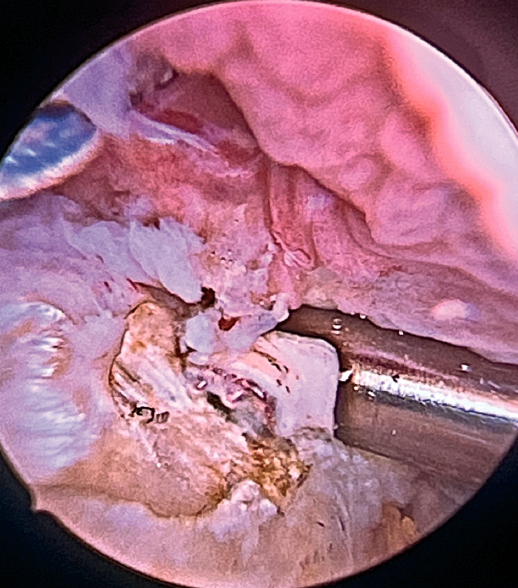

The greater tuberosity is then prepared with the bone drill, creating a bleeding bone surface to enhance tendon-bone healing, as this is where both cuff repair and augmentation with biceps will be carried out (Figure 1).